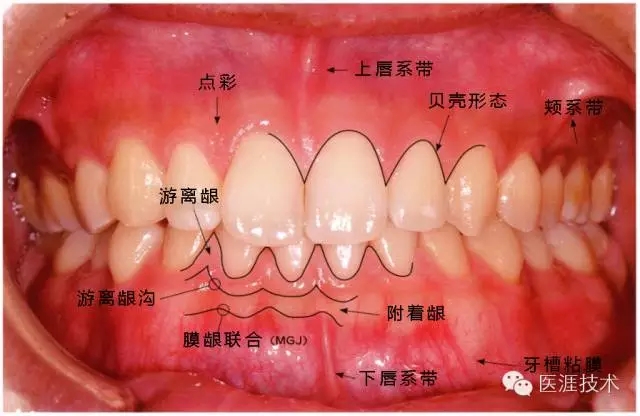

健康牙周組織的牙齦邊緣呈珊瑚粉,邊緣牙齦略呈圓弧狀。牙間可見三角形的牙間乳頭,牙齦邊緣相連呈貝殼形。

附著齦與游離齦相連時(shí),有時(shí)有游離齦溝存在(成人的30~40%)。

附著齦通過膠原纖維牢固結(jié)合骨骼與牙骨質(zhì),因此可見不可動、硬而緊繃的點(diǎn)彩(橘皮樣點(diǎn)狀凹凸)。

從牙齦牙槽粘膜到根尖有牙槽粘膜。牙槽粘膜為暗紅色,與骨骼結(jié)合較松,故可動。

健康且正常的牙周組織臨床圖像